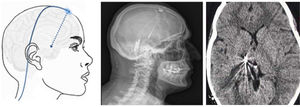

El componente sensitivo tiene tres divisiones: la primera, o rama oftálmica (V1); la segunda, o maxilar (V2), y la tercera, o mandibular (V3). La rama oftálmica proporciona inervación de la piel de la mayor parte de la nariz (puente, laterales, pared lateral de la cavidad nasal y septum), la frente, el párpado superior, el globo ocular y la glándula lacrimal. La segunda rama inerva la zona cigomática, las alas nasales, el labio superior, las encías de la arcada dentaria superior, el paladar, la nasofaringe, la cavidad nasal posterior y las meninges de la fosa craneal anterior y media. Finalmente, la tercera rama inerva la mucosa yugal, la sien y el cuero cabelludo lateral, el meato auditivo externo, la membrana timpánica, la articulación temporomandibular, la mandíbula y la arcada dentaria inferior, dos tercios anteriores de la lengua, el labio inferior y el mentón1,2 (fig. 1).

Ramas del trigémino y dermatomas de cada una de ellas.

V1: primera división del trigémino (oftálmica); V2: segunda división del trigémino (maxilar); V3: tercera división del trigémino (mandibular).

AT: nervio aurículo-temporal; B: nervio bucal; CF: nervio cigomático-facial; CT: nervio cigomático-temporal; IO: nervio intraorbitario; IT: nervio infratroclear; L: nervio lacrimal; M: nervio mentoniano; NE: nervio nasal externo; NOM: nervio occipital mayor; NOm: nervio occipital menor; SO: nervio supraorbitario; ST: nervio supratroclear.